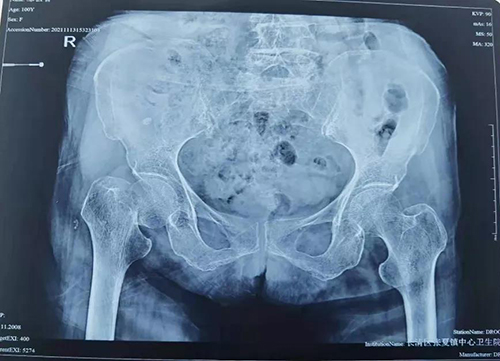

患者邹奶奶(化名)今年100岁了,因不慎摔倒致右侧股骨颈骨折,伤处疼痛难忍,不能活动,严重影响生活质量。此类患者若长期卧床,会出现各种并发症,最终危及生命,家属积极要求手术治疗。但由于老人年龄大、基础情况差,手术风险极大,当地医院难以处理,为求进一步治疗遂转入我院东院创伤二科。

患者超高龄,既往有胃炎病史,平日经常恶心,进食少,消瘦,营养状况欠佳,入院后术前化验检查示贫血、低蛋白血症、凝血障碍、心功能不全及肺部感染。为最大限度地帮助老人恢复部分生活自理能力,减轻痛苦,改善生活质量,以创伤中心常务副主任李连欣为首的专家团队,经过充分的术前检查及多科讨论,认为老人手术指征强,意义重大,虽有风险,但总体可控。经与家属沟通同意后,创伤中心首席专家周东升教授为老人施行了“人工股骨头置换术”。为加强术后监护及精细化管理,老人术后转入东院创伤四科(创伤重症病房)。